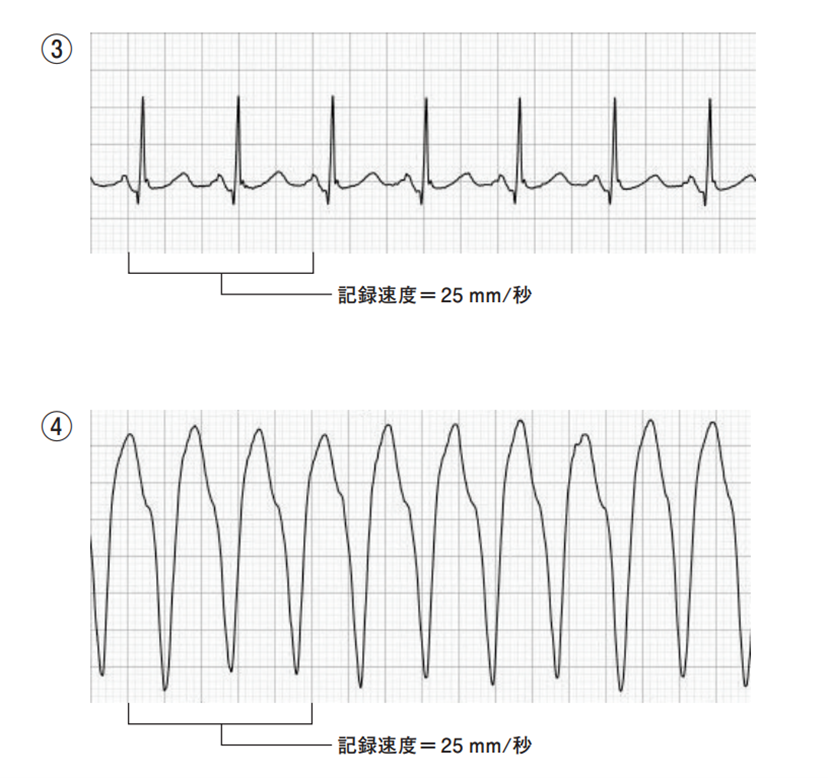

71ASbdgC9mL.jpg。第114回看護師国家試験 午前必修問題 | 一般財団法人厚生労働。2ページ目:第114回 看護師国家試験 解答速報 ただいま公開中。看護師国家試験2024年に使用していた国家試験対策のものです。・でた問 ¥1681・ここだけおぼける ¥1500+税・ゴロ勉 ¥1500+税・プチナース看護師国家試験過去問題集 ¥5940・クエスチョンバンク必修問題集 ¥3190・クエスチョンバンク国家試験問題解説 ¥6490・1番最新の国家試験で実際に私が解いた問題と添削した解答付きのもの(113回の国試問題)・その他問題集10冊プラスプリントは自分が模試を受けた解説に貰ったり、学校の授業で使用をしたものなので非売品ですが、解説がしっかり載っており非常に分かりやすく役に立ちました。これだけついてこの値段はかなりお得です。送料はこちらもちで配送はクロネコヤマトでします。。必修問題 – 114回看護師国家試験 – 心電図波形 心室脈拍。これさえやっていれば東進などの10万以上する高い講義に通っている方もいましたが、そういうものにお金を払わなくてもこれだけで私は250点以上は取れました。AGOS TOEFL 教材 2017年 CD8枚付き。メキメキ力がつく受験英語の集中講義。使用していたので安くしています。24年度卒 歯科衛生士教科書。KORON 警察 昇任試験 2024 1〜10。4月からは仕事で忙しくなるので3月中に購入いただけたらすぐにお送りできます。東進教材漢文。【25冊】ひろゆき 西村博之 全巻帯付き 2ちゃんねる 論破王 成田悠輔 ja。ご検討宜しくお願いします。希学園基礎計算問題集&難問計算問題集